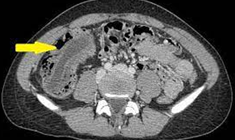

CT κοιλίας - MALToma τυφλού και παρακολικός λεμφαδένας (Ευγενική παραχώρηση Dr. V. Penopoulos)